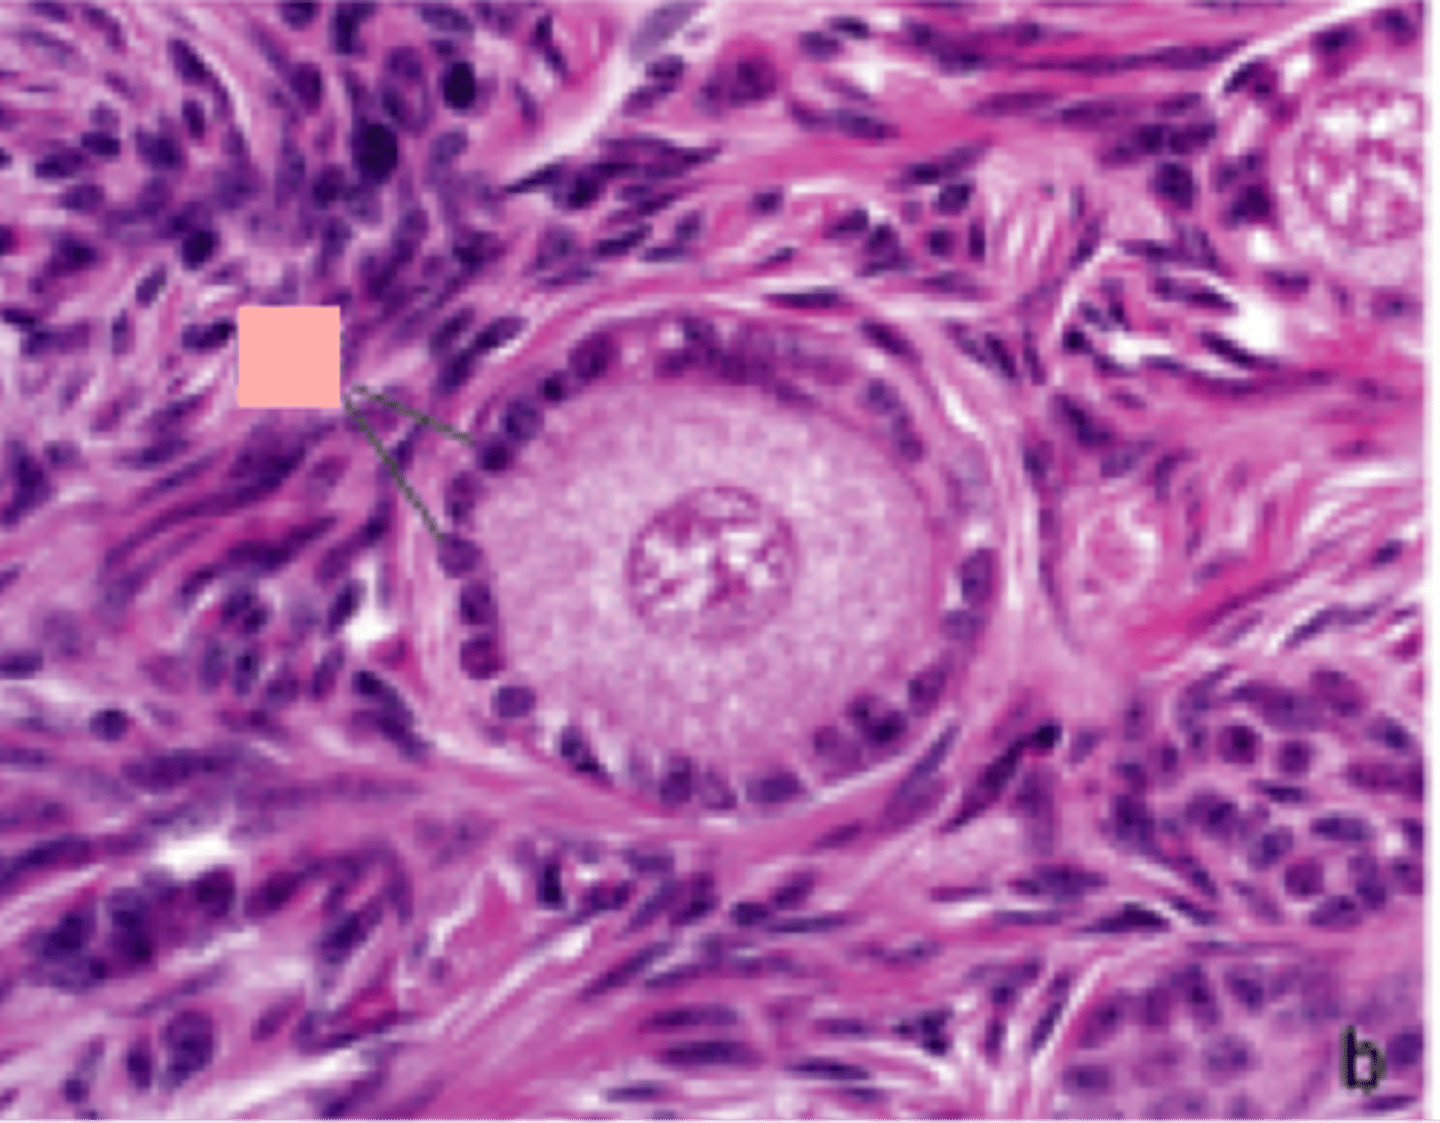

mature follicle

ignore arrow

antrum

corona radiata

cumulus oophorus

purple dots going around the small circle

follicular fluid

granulosum cells

what is the cumulus oophorus made of

stratum granulosum

SG to the right of it is the basement membrane

theca interna

theca externa

zona pellucida